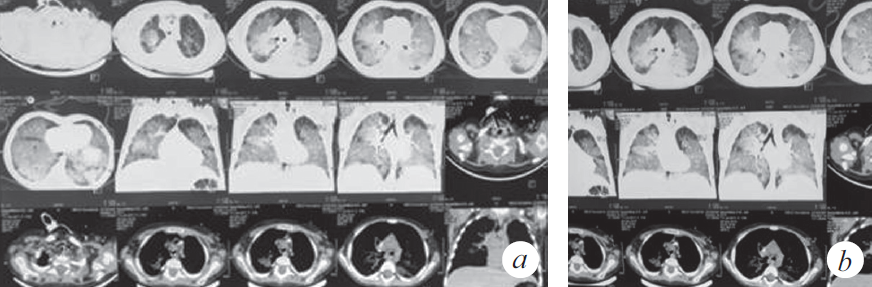

Продуктивный кашель с затрудненной эвакуацией мокроты впервые появился 12.12.2018, нарастала дыхательная недостаточность (одышка, кислородная зависимость), клинически и рентгенологически диагностирован спонтанный пневмоторакс справа (купирован дренированием). Во время дренирования развилась депрессия сердечной деятельности с переходом брадикардии в асистолию, с восстановлением ритма в течение 1 мин. после однократного введения адреналина и закрытого массажа сердца (15 с). Ребенок был переведен на искусственную вентиляцию легких (ИВЛ) (респиратор Savina, Dräger, Германия), отмечалась потребность в FiO2 0,6 для поддержания SpO2 92–95 %. Параметры вентиляции: SIMV, MV 6–7 мл/кг, PIP от 20 до 22 мбар; PEEP (режим BiPAP): минимум 4 мбар, максимум 8 мбар. На следующий день выполнена нижняя трахеотомия и установлена трахеостомическая канюля. Пациентка находилась на ИВЛ 2 мес. со стабильными показателями вентиляции, достигнутое снижение уровня респираторной поддержки было незначительным: PIP 16 мбар, FiO2 0,5, PEEP 4–6 мбар. Динамика газов венозной крови положительная: РО2 50–64 мм рт. ст., SvO2 74–82 %. Динамика КТ представлена на рис. 3–6. В целом томографические изображения характеризовались стабильностью, отличия связаны с эпизодами госпитальной пневмонии: зафиксировано 5 клинически ярких рецидивов. Конец второго месяца заболевания осложнился развитием диарейного синдрома клебсиеллезной этиологии, что заставило редуцировать объем питания на неделю. С декабря до марта отмечен отрицательный баланс по массе тела (минимальный показатель массы тела 8050 г).

Рис. 3. Компьютерная томография органов грудной клетки (через 8 нед. от дебюта заболевания) (a). Сохраняются КТ-признаки паренхиматозного поражения легочной ткани, отмечена положительная динамика в виде уменьшения плотности легочной консолидации (b)

Fig. 3. CT of the chest organs (8 weeks after the onset of the disease) (a). CT-signs of parenchymal lesion of the lung tissue are preserved, positive dynamics in the form of a decrease in the density of pulmonary consolidation are noted (b)

Рис. 4. Компьютерная томография органов грудной клетки (через 11 нед. от дебюта заболевания) (a). КТ-признаки преимущественно базального паренхиматозного поражения легочной ткани, появление выпота в правой плевральной полости (b)

Fig. 4. CT of the chest organs (11 weeks after the onset of the disease) (a). CT signs of a predominantly basal parenchymal lesion of the lung tissue, the appearance of effusion in the right pleural cavity (b)

Рис. 5. Компьютерная томография органов грудной клетки (через 4 мес. от дебюта заболевания) (a). КТ-признаки диффузного субтотального поражения легочной ткани с зонами консолидации в базальных отделах S2, S6, S10 справа и S6 слева, вероятно воспалительного характера (b)

Fig. 5. CT of the chest organs (4 months after the onset of the disease) (a). CT signs of diffuse subtotal lesion of the lung tissue with areas of consolidation in the basal sections S2, S6, S10 on the right and S6 on the left, probably of an inflammatory nature (b)

Рис. 6. Компьютерная томография органов грудной клетки (через 5 мес. от дебюта заболевания) (a). КТ-признаки интерстициального поражения легочной ткани с увеличением площади консолидации в медиальных отделах обоих легких с сохранением в базальных отделах S2, S6, S10 справа и S6 слева (b)

Fig. 6. CT of the chest organs (5 months after the onset of the disease) (a). CT signs of interstitial damage to the lung tissue with an increase in the area of consolidation in the medial sections of both lungs, while maintaining in the basal sections S2, S6, S10 on the right and S6 on the left (b)